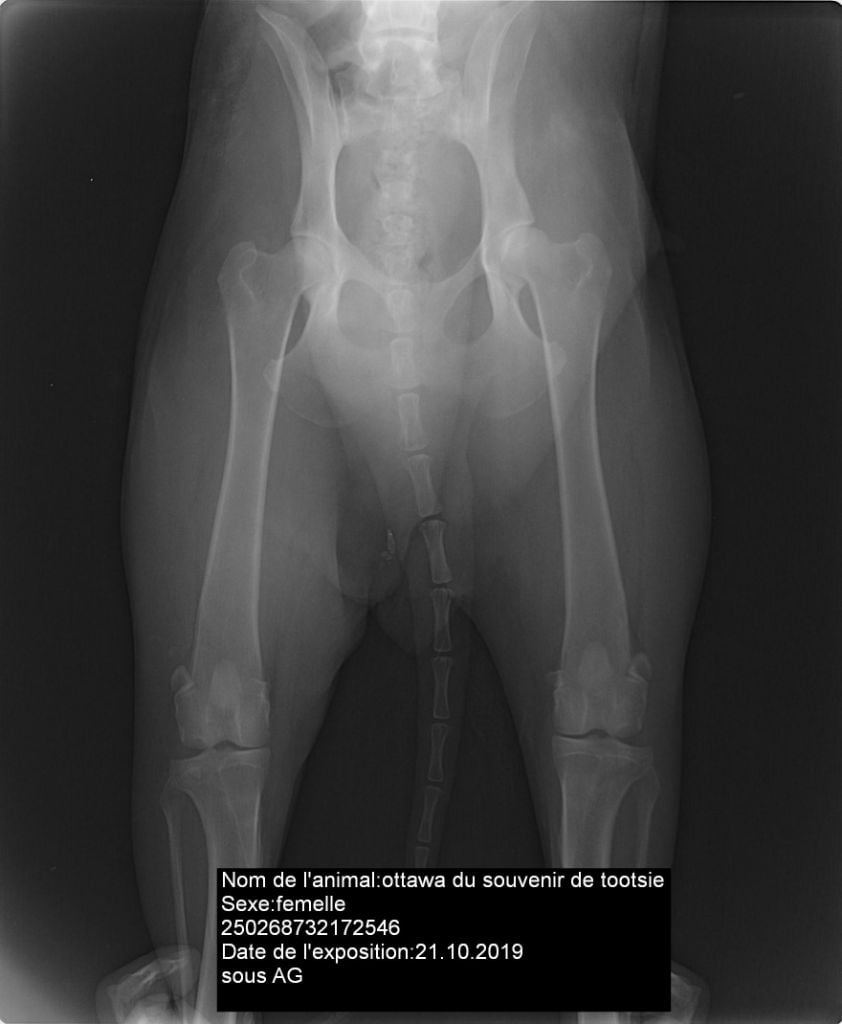

Chien Eurasier Ottawa Du Souvenir De Tootsie

250268732172546

luxation de rotule - indemnedysplasie de la hanche - Indemne ADandy walker - indemne par parenté